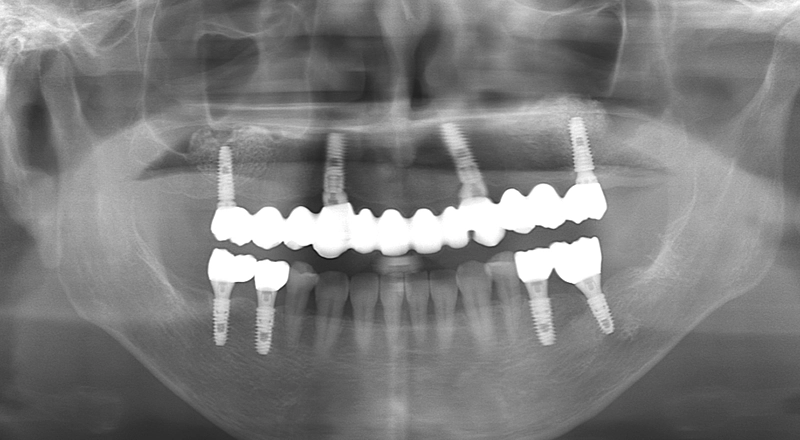

| 主訴 | 義歯が合わず食事の時に外している。しゃべり辛い |

|---|---|

| 診断名 | 義歯不適合 |

| 年齢・性別 | 50歳・⼥性 |

| 治療期間・回数 | 1年・24回 |

| 治療方法 | サイナスリフト、オールオンフォー |

| 費用 | 5,324,400円 最高プラン (費用を抑えたプランも提案可能) |

| 治療上のリスク |

|